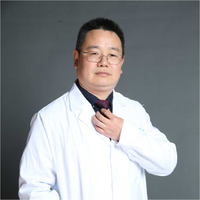

先看2019年时的影像:

病灶出现,密度不纯,有点状高密度成分,表面不光滑不平整。

实性成分为主,但边缘缺乏膨胀性,长刺较细长,感觉更像慢性炎。